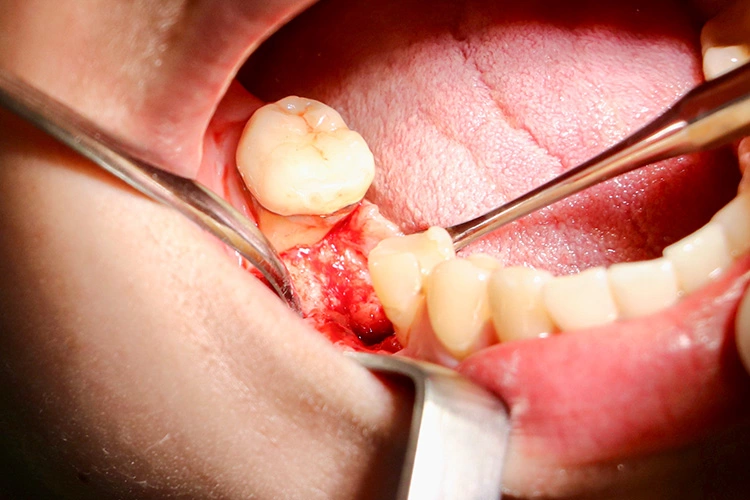

Im nächsten Schritt erfolgte die vollständig navigierte Implantation des Microcone-Implantates (Ø 5,0 mm, 9 mm Länge) in der Region 46 (Abb. 8-14) nach dem vom Hersteller empfohlenen Bohrprotokoll, das sich nach Knochenqualität und Implantatdurchmesser richtet. Die Chirurgie-Kassette (Abb. 6) ist übersichtlich aufgebaut und intuitiv zu bedienen. Zur schonenden Präparation des knöchernen Implantatbetts stehen je nach Implantatdurchmesser und Knochenqualität bis zu fünf verschiedene Bohrertypen mit Farbcodierung zur Verfügung. Das Implantat war für eine gedeckte Einheilung vorgesehen und der Kieferkamm wurde durch Nahtlegung speicheldicht verschlossen (Abb. 15).